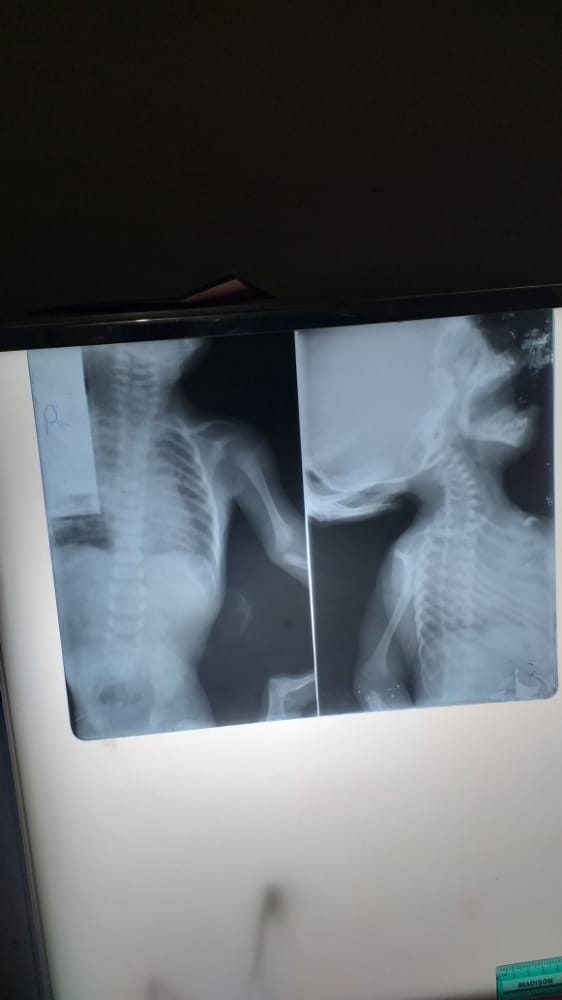

The plain chest radiograph showed normal heart size, with normal lung fields and chest wall, the abdominal radiograph showed pockets of lucencies in the right and left hemi-abdomen, and the region of the pelvic cavity conforming to bowel gas shadows in the gastrointestinal tract most likely from a distal tracheoesophageal fistula (figures 1 &2).

Figure 1: Plain radiograph of the chest; anterior-posterior view demonstrating normal heart size and contour, left-sided aortic arch, normal lung-fields, normal thoracic wall, vertebral spine and normal dmonstrated bones of the upper limbs bilaterally.

Figure 2: Plain radiographs; left image: anterior-posterior view of chest and abdomen demonstrating pockets of lucencies in the right and left hemi-abdomen and the pelvic region most likely from a distal tracheoesophageal fistula. Normal chest and demostrated vertebral spine. The right image: an attempted laterl demonstrating the cervical, thoracic and part of the lumbar spine, all appear normal. Note a lead blcker on the chest denoting the right aspect of the image.